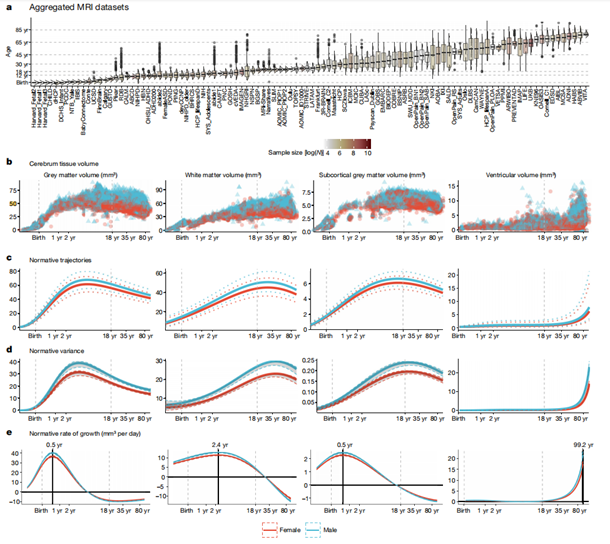

因此,如图1a所示,研究创建了一系列跨越人类整个生命周期的大脑图表,从15周大的胎儿到100岁的成年人。显示了人类大脑在生命早期迅速扩张,并随着年龄的增长而缓慢萎缩的变化过程。

研究人员使用基于位置、尺度和形状的广义加法模型(GAMLSS)创建了人类寿命的大脑图表。具体研究方法为,将GAMLSS模型拟合到大脑的四个主要组织体积的结构性磁共振成像数据上。如图1b-e所示,依次为,总皮质灰质体积(GMV)、总白质体积(WMV)、总皮质下灰质体积(sGMV)和总脑室脑脊液体积(脑室或CSF)。

研究人员利用大脑图表,首次确认了人类大脑的发育里程碑。例如大脑的主要组织在什么年龄阶段达到体积峰值以及大脑的特定区域何时发育成熟。使研究人员能够度量在大脑中非常早期的、快速的变化;以及随着年龄的增长,大脑长期而缓慢的衰退。研究结果发现:

从妊娠中期开始,脑灰质(脑细胞)的体积迅速增加,并5.9岁时达到顶峰,然后体积开始缓慢下降。

从妊娠中期到儿童早期,脑白质(大脑连接)的数量也迅速增加,并在28.7岁时达到峰值。

50岁后,脑白质体积的开始加速下降。

皮层下的灰质(控制身体功能和基本行为)体积,在青春期14.4岁时达到顶峰。

相比之下,脑脊液在2岁之前呈增长趋势,之后呈稳定状态直至30岁前,然后缓慢呈线性增长,在60岁时开始呈指数增长。灰质个体差异在早期发育过程中增加,在4岁时达到峰值,而皮层下灰质变异性在青春期后期达到峰值。白质个体间变异在40岁时达到峰值,而脑脊液在人类寿命结束时变化最大。

图1:人脑图表